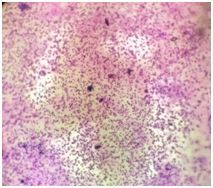

25% Haemtocrit Schizont stage with haemozoin pigments

140x Magnification

Microscopic view

foldscope view